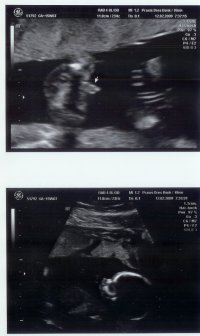

• SSW 16.jpg

SSW 16.jpg

130,9 KB · Aufrufe: 370